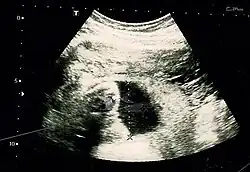

A suspeita de gravidez abdominal surge quando a anatomia fetal pode ser facilmente palpada, ou quando o apresentação é anormal, o colo uterino está deslocado, ou há falha na indução do parto.[1] Radiografias podem auxiliar no diagnóstico.[11] A ultrassonografia pode demonstrar que a gestação está fora de um útero vazio, com pouco ou nenhum líquido amniótico entre a placenta e o feto, ausência de parede uterina envolvendo o feto, partes fetais próximas à parede abdominal, apresentação anormal do feto, placenta de aparência anormal e presença de líquido livre no abdômen.[8][18] A ressonância magnética também tem sido usada com sucesso no diagnóstico e no planejamento cirúrgico da gravidez abdominal.[16][19] Níveis elevados de alfafetoproteína também podem indicar a presença de gravidez abdominal.[20]

Ultrassom

A maioria dos casos pode ser diagnosticada por ultrassonografia.[21] Entretanto, o diagnóstico pode ser perdido dependendo da habilidade do operador.[7][22]